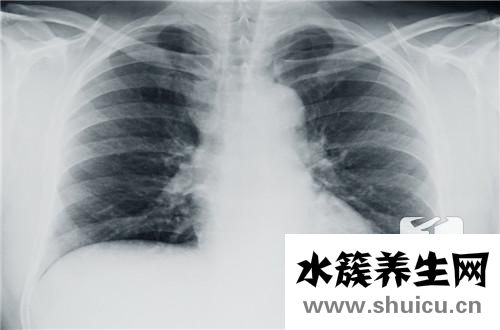

來兒科就醫的病人中,很多人有咳嗽、咳嗽有痰、胸悶氣短、喘氣、咯血等呼吸道癥狀,此刻,病人通常會積極規定醫師為自己做下胸部透視或肺部ct查驗。但即便肺部ct結果是一切正常的,醫師還會繼續規定病人再做胸部CT的查驗。許多 病人搞搞不懂,本來肺部ct是一切正常的,為何還需要做胸部CT的查驗哪?實際上這不難理解,由于肺部ct是將皮膚、肌肉、骨骼、心臟、肺、淋巴結等多種多樣組織、人體器官重合在一起拍的一張影片,因此 一些細微的變病如小結節、早期肺癌、輕度的肺纖維化、支擴、藏匿位置的肺炎、支氣管狹窄等在肺部ct上難以發覺,非常容易導致誤診和錯診。

而胸部CT是橫剖面的掃描儀,等同于把一個西瓜割開看來,里里外外都能見到,數據量更大,看的更全方位和詳盡,連一些微小的變病和藏匿位置的問題都可以發覺。

例如哮喘,哮喘是一個唯一性的確診,一切正常狀況下哮喘的肺部ct或胸部CT應該是基本一切正常的。但臨床醫學上面有許多 患者表層上看上去像哮喘,但在醫治全過程中治療效果不太好,進一步做胸部CT查驗發覺是支氣管異物、支氣管狹窄、支氣管炎子宮內膜結核病、肺臟腫瘤等狀況,因而哮喘確診的情況下我們規定病人基本開展胸部CT的查驗,便是要防止有關病癥的誤診和錯診。